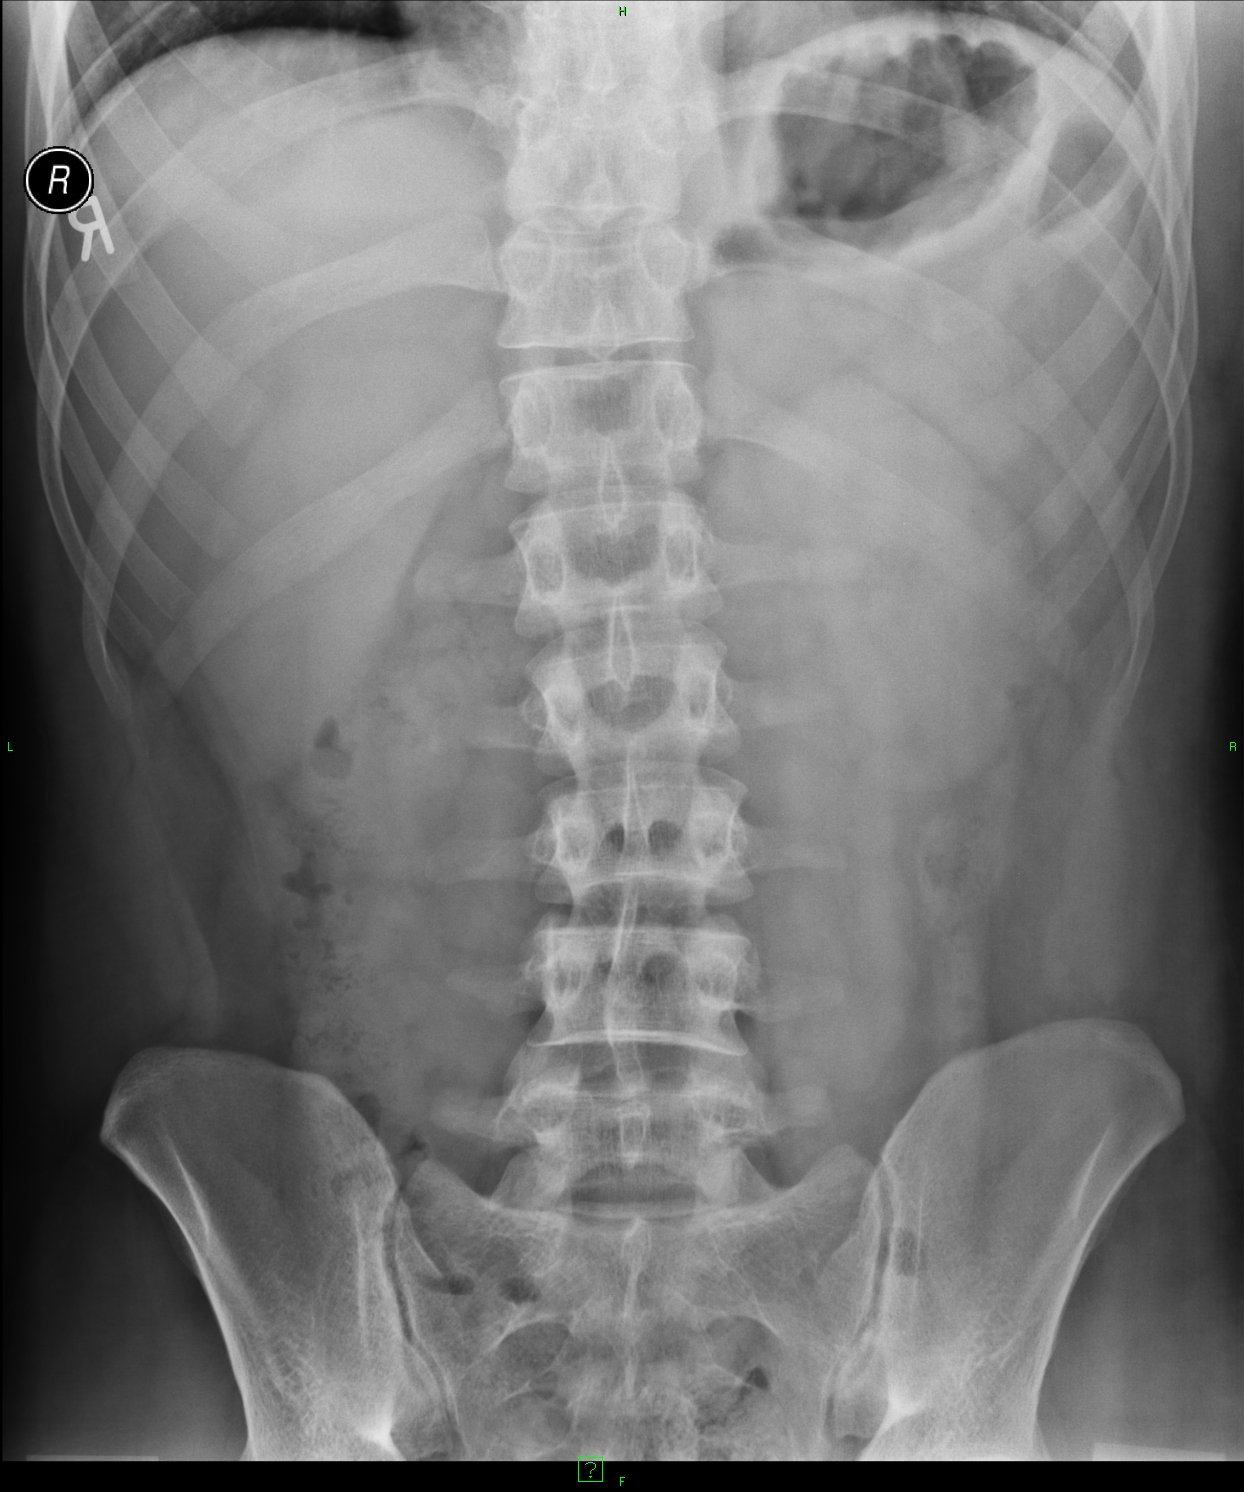

In a typical case, the liver shadow is located under the diaphragm on the right side on the conventional abdominal radiograph. (Figure 2) .

Figure 2.: Hepatomegaly, native abdominal X-ray